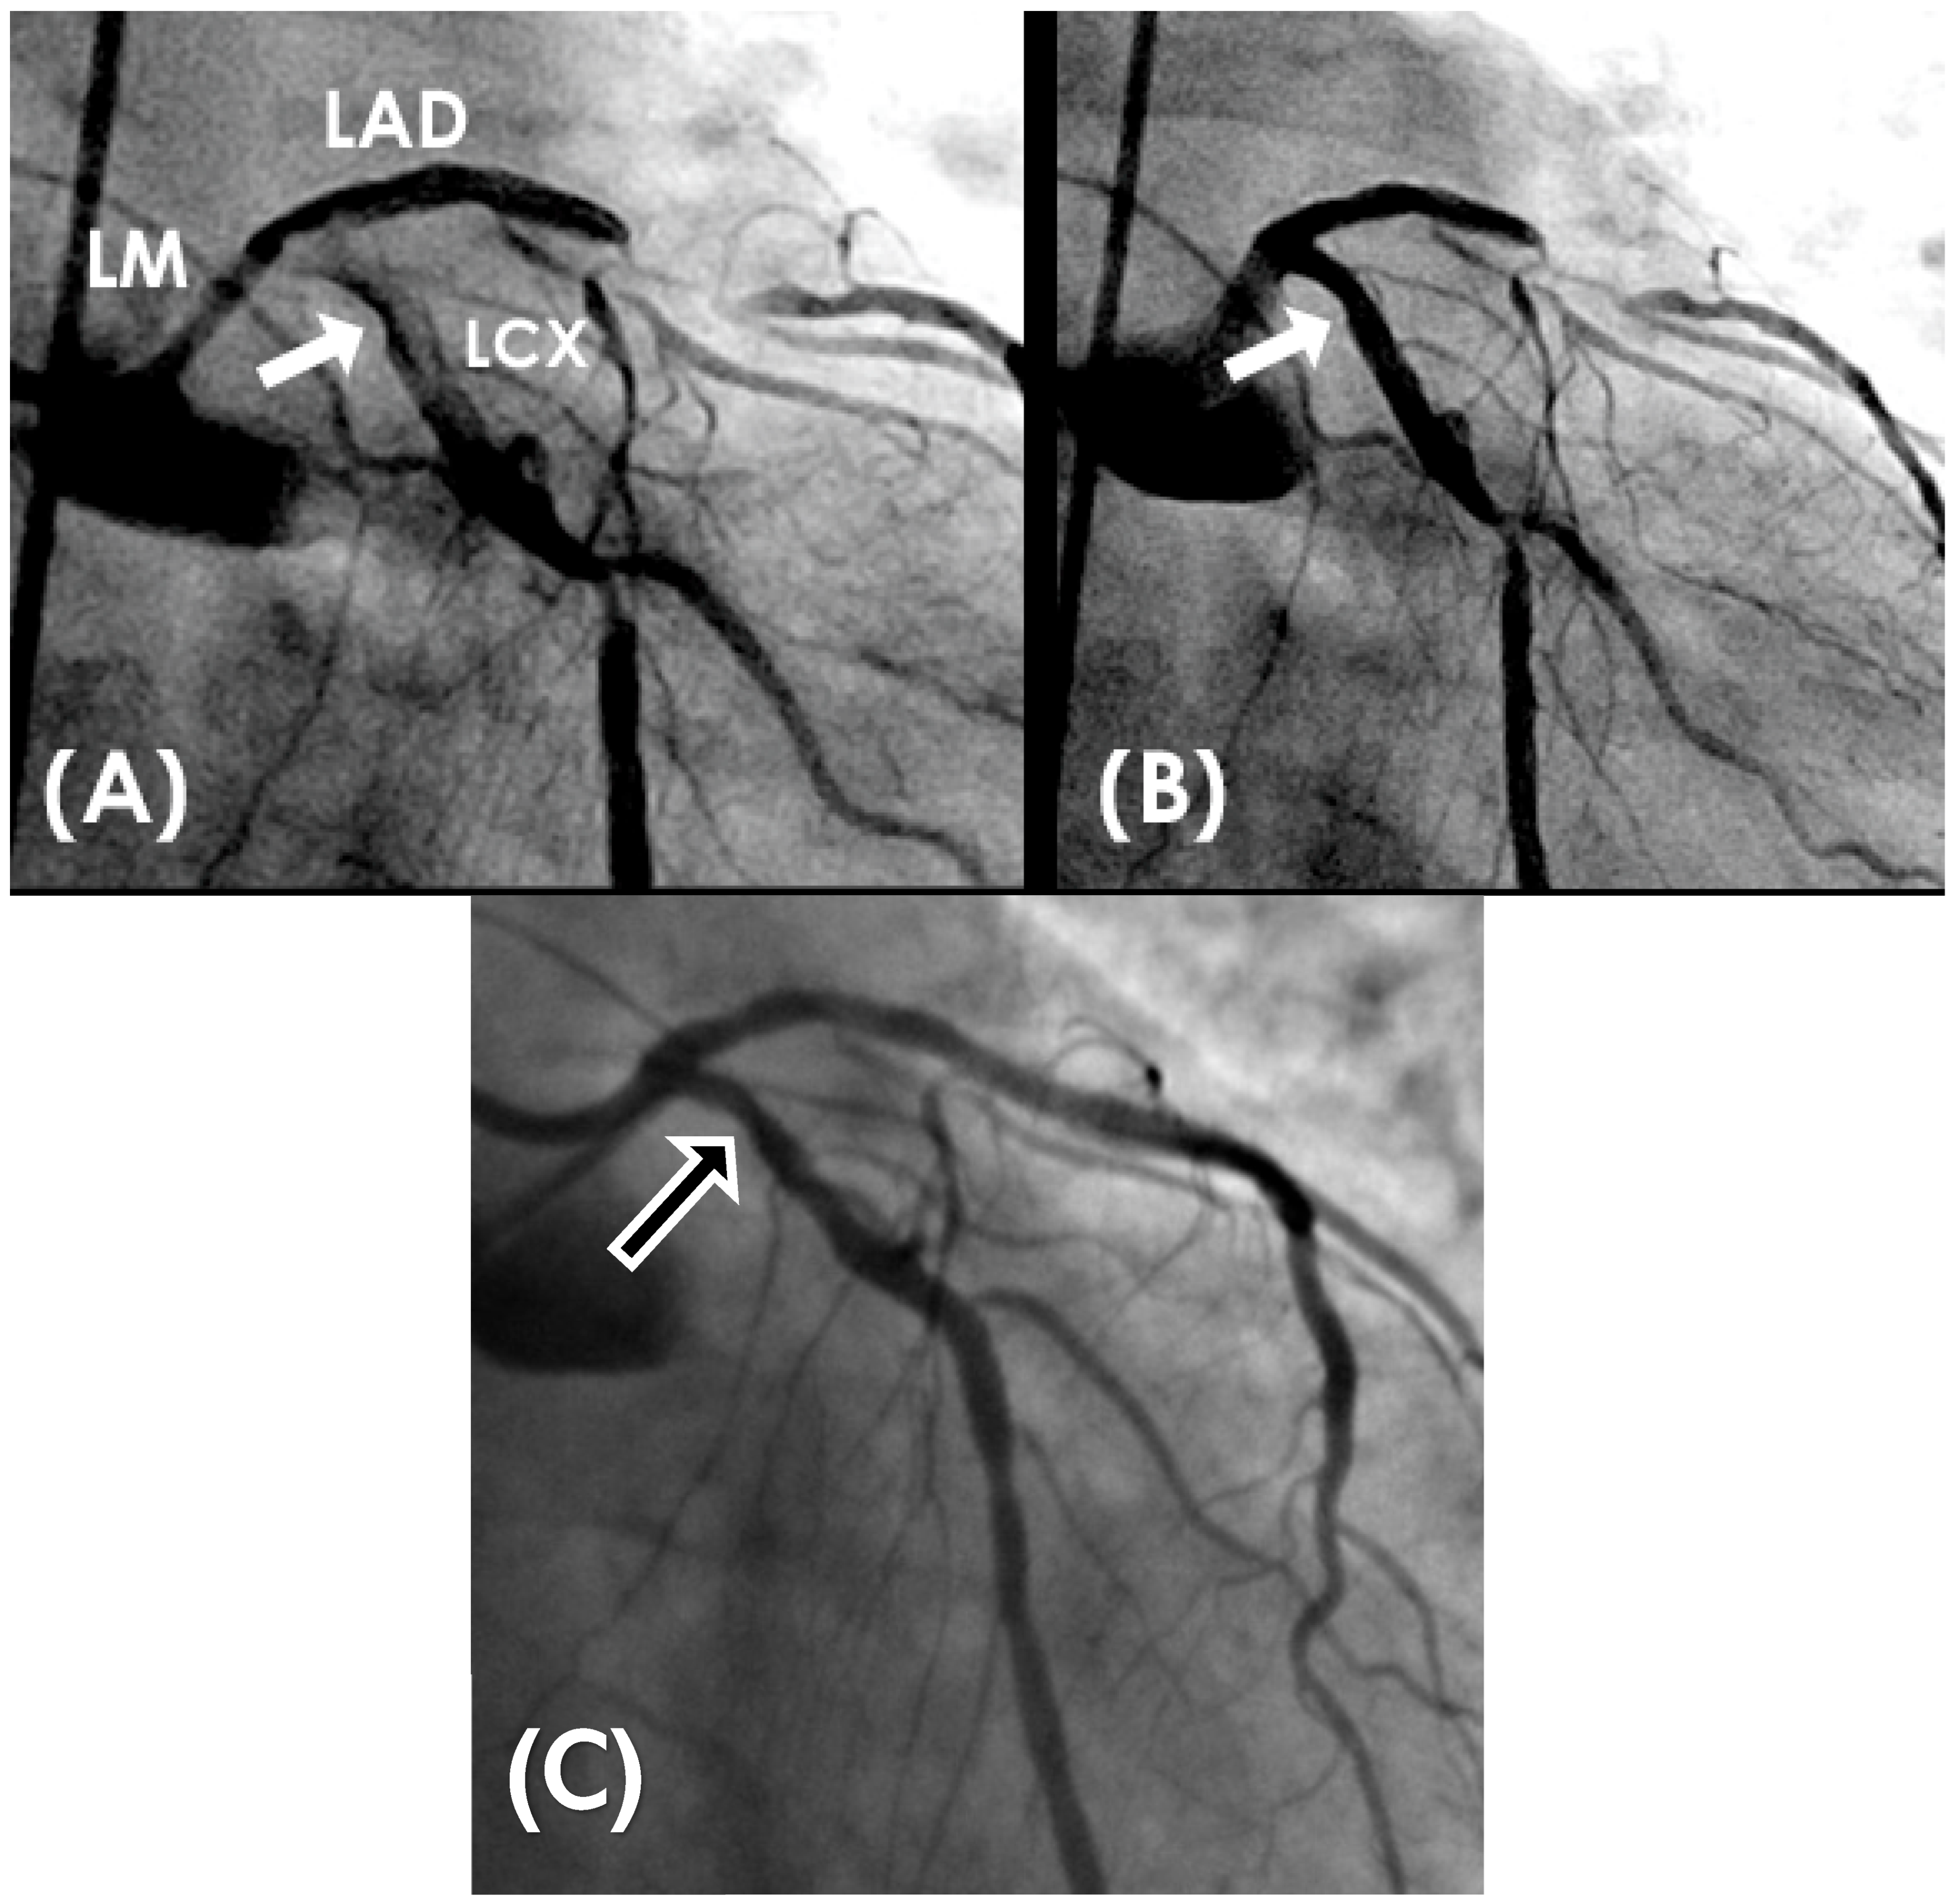

2.4. Recirculating Flow

- Fluid Mechanics Perspective:

- Coronary Angiographic Perspective:

2.5. Collision Secondary to Water Hammer Shock

- Coronary Dynamics Perspective:

2.6. Codification of Lesions and Creation of a Coronary Acoustic Map